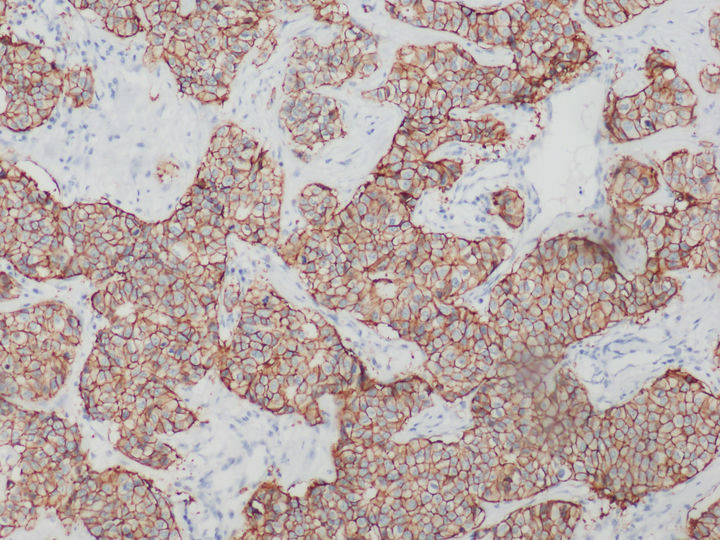

HER是一類與細(xì)胞增殖息息相關(guān)的蛋白質(zhì),全稱是human epidermal growth factor receptor,中文叫作人表皮生長(zhǎng)因子受體。HER蛋白質(zhì)家族共有四兄弟,其中HER2負(fù)責(zé)將細(xì)胞膜外的生命信息傳導(dǎo)至細(xì)胞內(nèi),是乳腺癌診斷指標(biāo)之一,檢測(cè)HER2一般用正置熒光顯微鏡,使用免疫組化或熒光原位雜交FISH技術(shù)。

在乳腺癌,胃癌等腫瘤篩查領(lǐng)域中,HER2的表達(dá)水平是腫瘤檢測(cè)的常用指標(biāo)。目前,HER2基因檢測(cè)常見方式以免疫組化IHC技術(shù)和FISH技術(shù)為主。

免疫組化HER2檢測(cè)可以用普通顯微鏡明場(chǎng)觀察實(shí)現(xiàn),設(shè)備要求較低,但靈敏度和特異性相對(duì)弱。